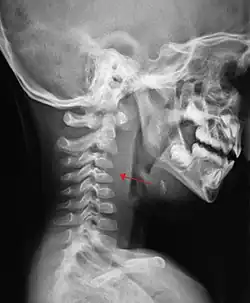

| A lateral cervical spine X-ray demonstrating prevertebral soft tissue swelling (marked by the arrow) as seen in a person with a retropharyngeal abscess | |

X-ray of the neck often (80% of the time) shows swelling of the retropharyngeal space in affected individuals. If the retropharyngeal space is more than half of the size of the C2 vertebra, it may indicate retropharyngeal abscess.[5]